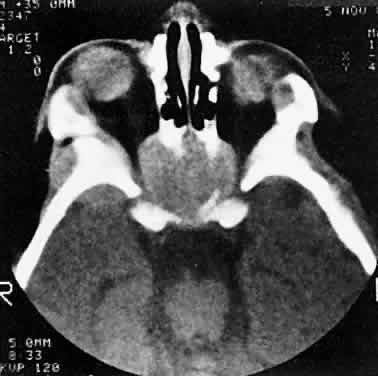

Sporadic North American cases have a less-definitive viral association. These patients differ clinically in their age of presentation (mean, 11 years) and in the usual site of tumor origin (intra-abdominal lymphoid tissue).40,41 Involvement of the facial bones and orbit is less common in the North American cases, but invasion of the orbit from the sinuses may occur42,43 (Fig. 4).

Fig. 4. Burkitt's lymphoma involving the posterior ethmoids, skull base, and both orbital apices in a 5-year-old boy.